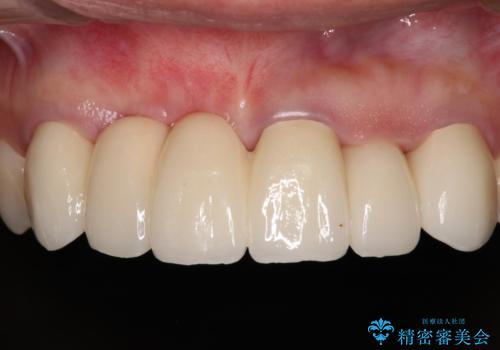

1回の歯肉移植により歯肉の厚みは大幅に改善されましたが、折角なのでもう少し大きくしたいとの要望があり、2回目の処置も行うこととしました。

厚みも高さも十分な歯肉量を獲得することができました。